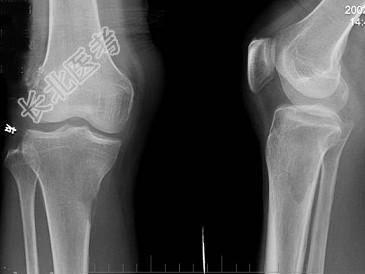

- 单项选择题男,59岁, 右小腿近端疼痛1年,活动障碍半年, 有前列腺癌病史,请结合所提供图像, 选择最佳答案 ( )

C、右胫骨骨转移